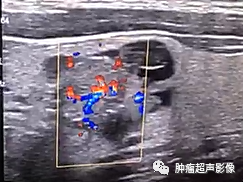

4、CDFI:实性部分丰富动脉血流,尤其是由中心向四周发出的分支动脉血流特异性较高(“烟花征”)。

来自微信会诊病例:形态不规则,微钙化,实性部分向周边的壁伸出多个较细的分隔(“蜘蛛征”),血流由中心向四周发出的分支动脉血流(“烟花征”)符合典型囊性乳头状癌,术后病理证实为乳头状癌